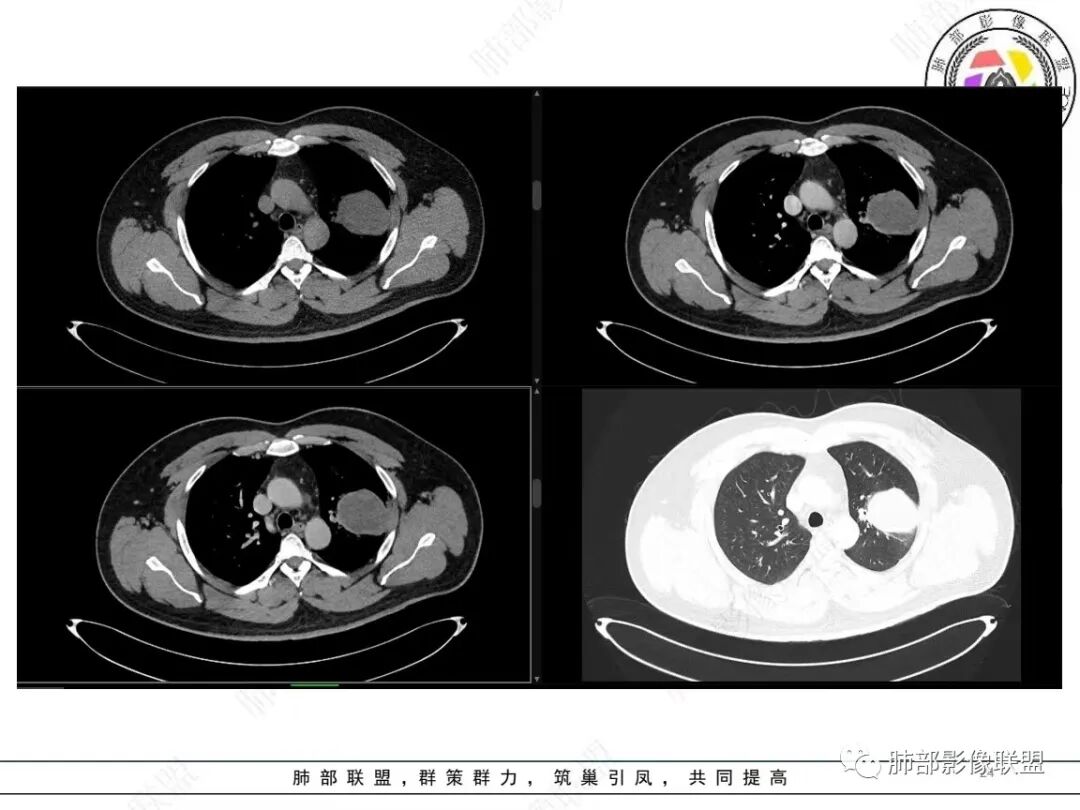

中年人,咳血,左肺上叶实性团块,边界清晰,与胸膜分界不清,可见栽赃表现,病灶推挤支气管及肺血管内移,增强可能条纹血管影,总体强化明显,考虑恶性或交界性肿瘤,间叶组织来源,肉瘤,SFT,肉瘤样癌,滑膜肉瘤。

左肺上叶胸膜肿块,浅分叶,边缘光整,密度不均匀,周围气管及血管受压推移,边缘强化,考虑肉瘤,鉴别SFT

左肺上叶占位,平扫密度较低,临近胸膜栽赃桩,外向内生长,边缘有膨隆、毛糙,增强后轻度强化,边缘弧线样强化,考虑肉瘤样癌

左上肺软组织肿块,周围散在磨玻璃影,界不清,窄基底贴于胸壁,胸膜下脂肪间隙不清,呈低强化,胸膜下见。与主病灶强化方式一样的病变,2R区见肿大淋巴。考虑恶性,间叶组织来源合并出血。

青年男性,咯血;CT示左肺上叶胸膜下软组织肿块,边界尚清,宽基底与胸膜相连,增强动脉期内见细条状血管影,轻度延迟强化,定位:肺外,胸膜外脂肪存在,考虑脏层胸膜起源;定性:考虑SFT。

影像表现:左肺上叶占位合并出血,胸膜栽赃,边缘强化,局部见血管影,中心密度20Hu,无强化,符合非液化坏死。定位:肺内,定性恶性(明显血管影,栽赃排除错构瘤,中心无强化排除PSP,无明显清楚的坏死边界,强化不符合肉芽肿,排除结核),年龄轻,无长时间吸烟史和肺气肿改变,肉瘤样癌可能性很小,与支气管无确切关系,所以病理类型考虑来源于肺间叶组织的肉瘤,骨外尤文?滑膜肉瘤?

有血供,强化不明显,周围肺出血,肺组织受压改变,定位肺外,胸膜增厚,部分胸膜下脂肪间隙存在,不确定肋骨是否受侵犯,部分层面与肺动脉分界不清,感觉推移,如果供血要考虑sft,强化不符合,有血管进入,但是强化不明显,密度相对均匀,所以不考虑坏死,富含粘液可能,咯血,说明累及支气管了,有一定侵袭性,肿块大,考虑间叶来源肿瘤,与胸膜接触面相对不是宽基底,综合考虑滑膜肉瘤可能,典型的滑膜肉瘤一般铺路石改变,这个又觉得信号相对均匀了一些学习中